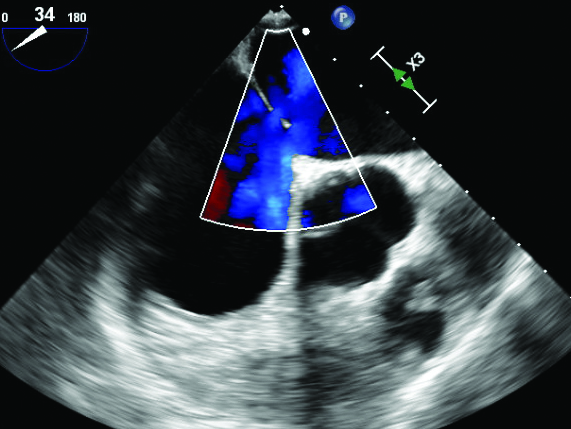

Figure 4

Figure 4. Transesophageal echocardiogram color Doppler displaying shunting through 1.6 cm ostium secundum atrial septal defect with superior fenestration.